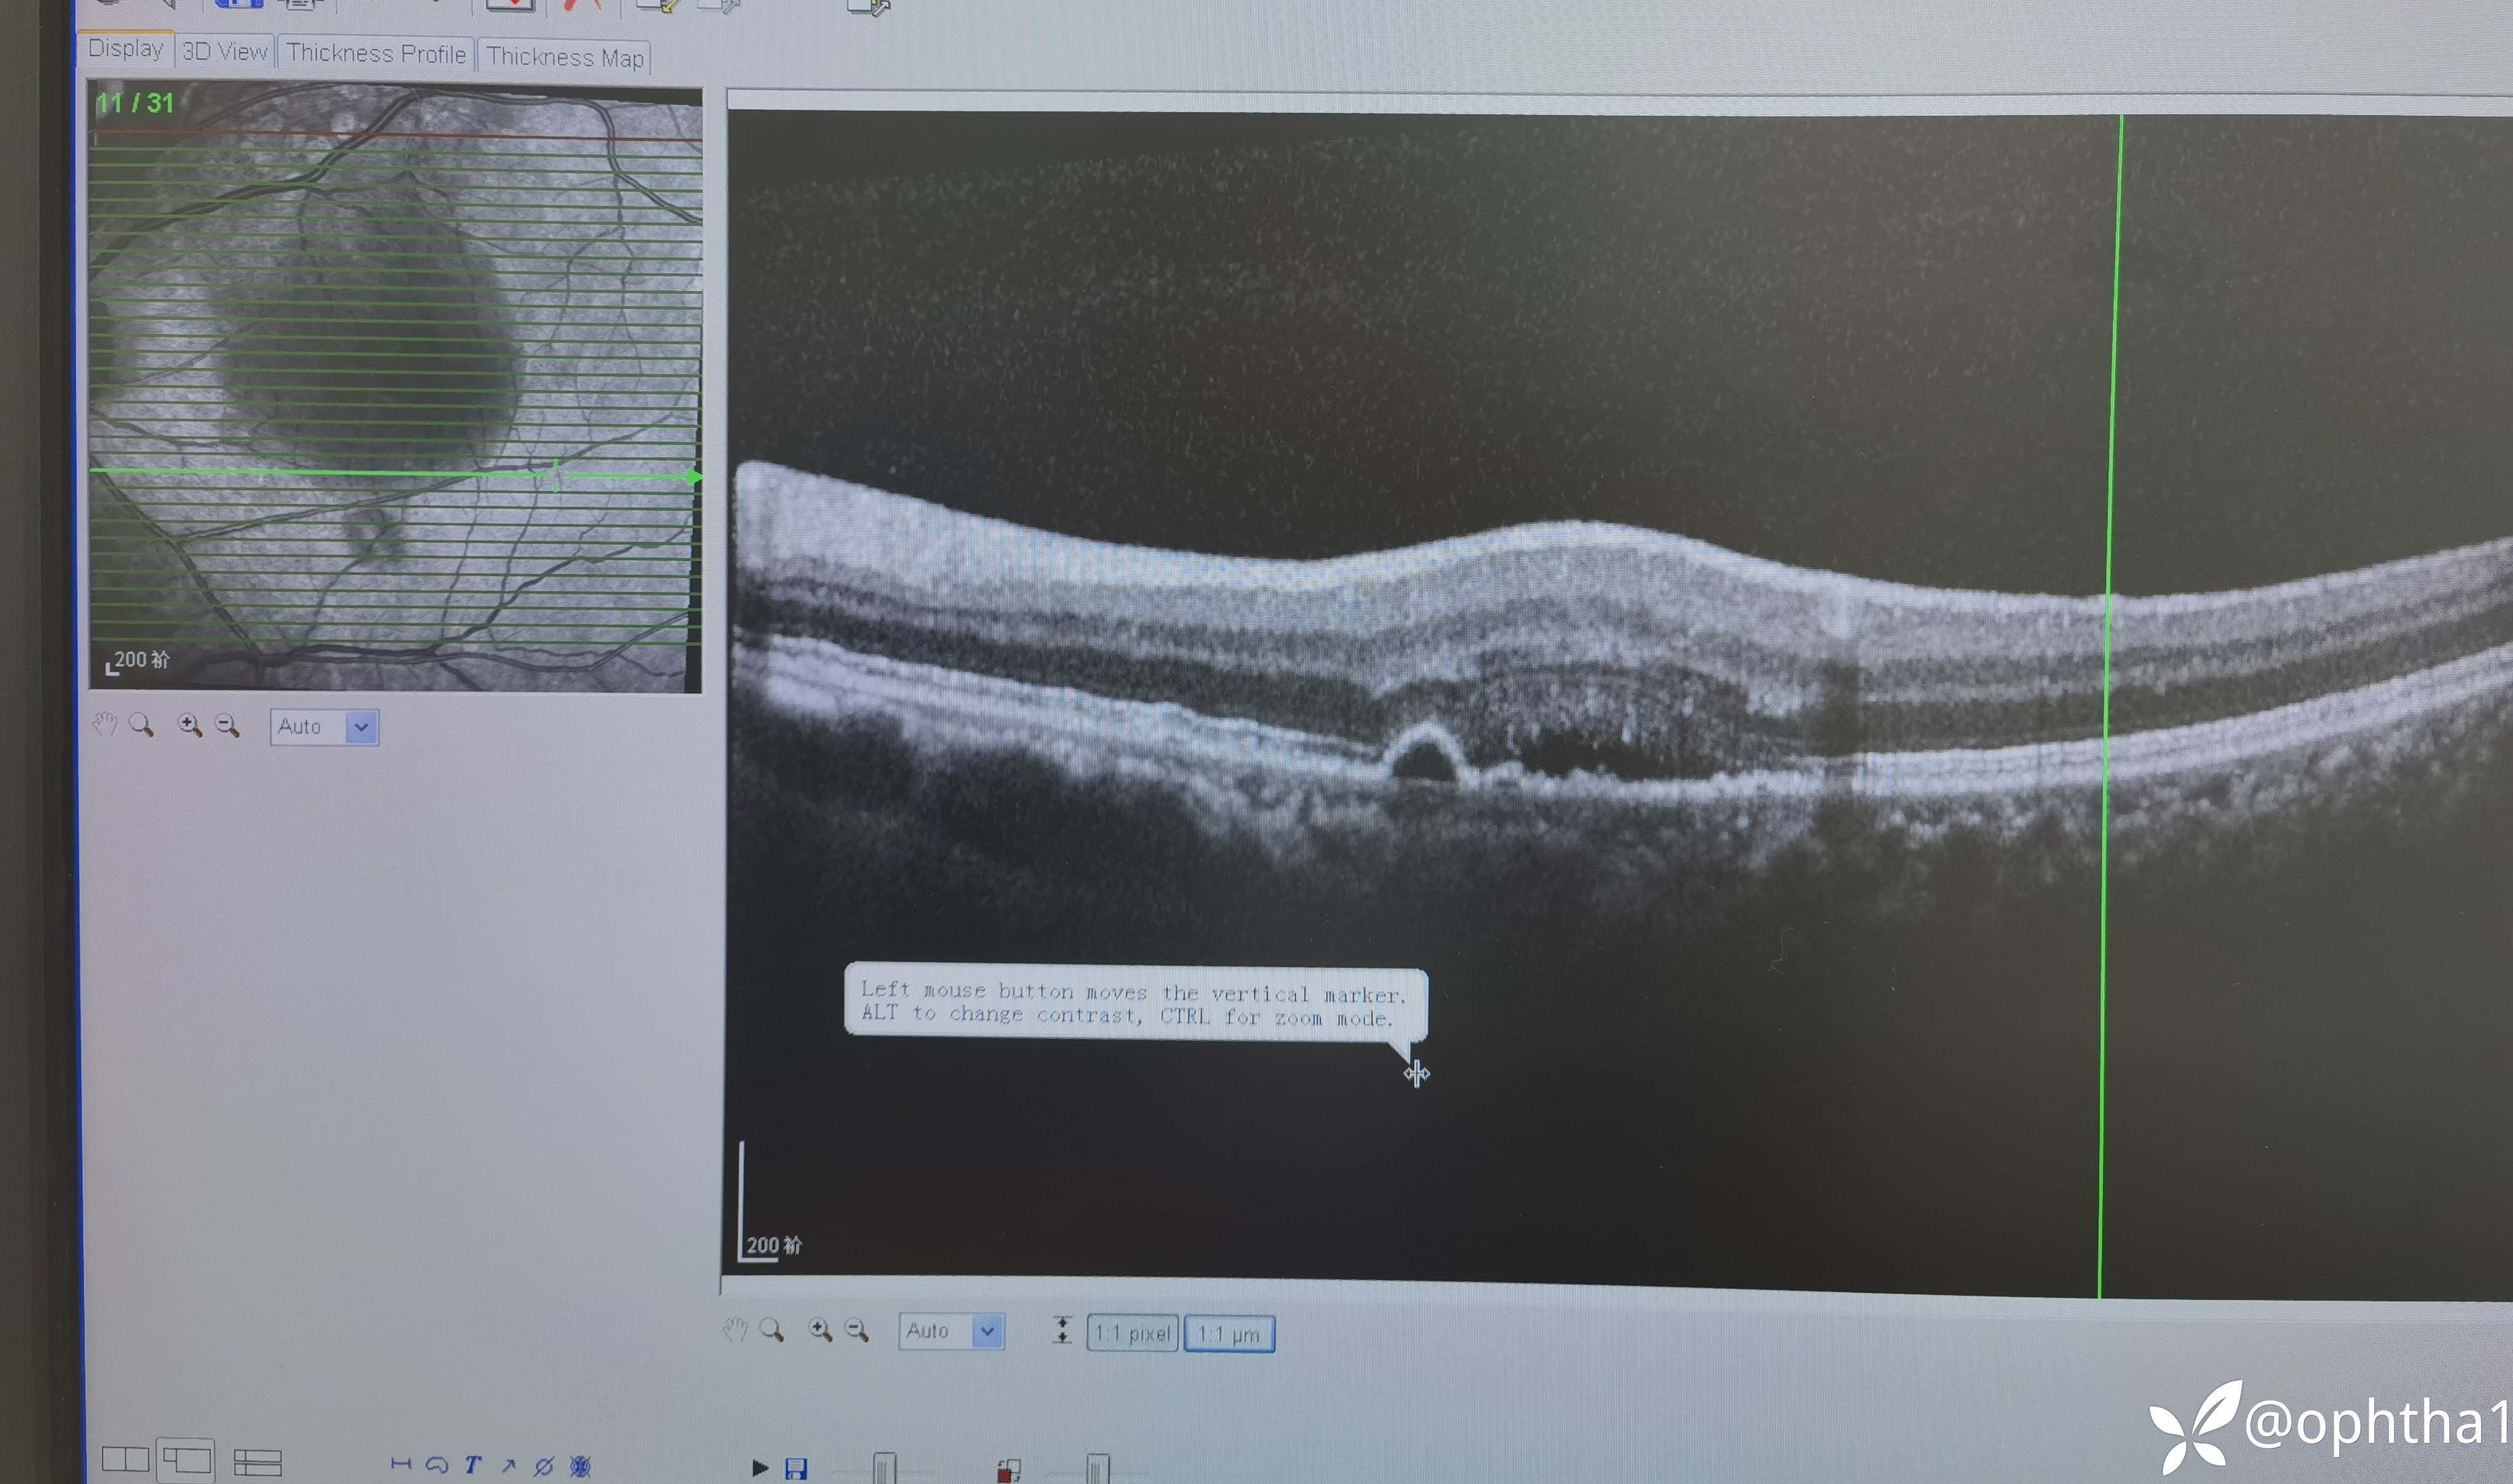

女性患者,59岁,高血压病史,余无特殊。1年前黄斑水肿外院抗VEGF一次,之后水肿完全消退,一直都很好,1个月前再次视物模糊,今天来我这要求再次注药。

现在的检查

求教各位老师考虑什么诊断?下一步需要完善检查?上方血管弓病灶是否需要多波长激光或TTT处理?